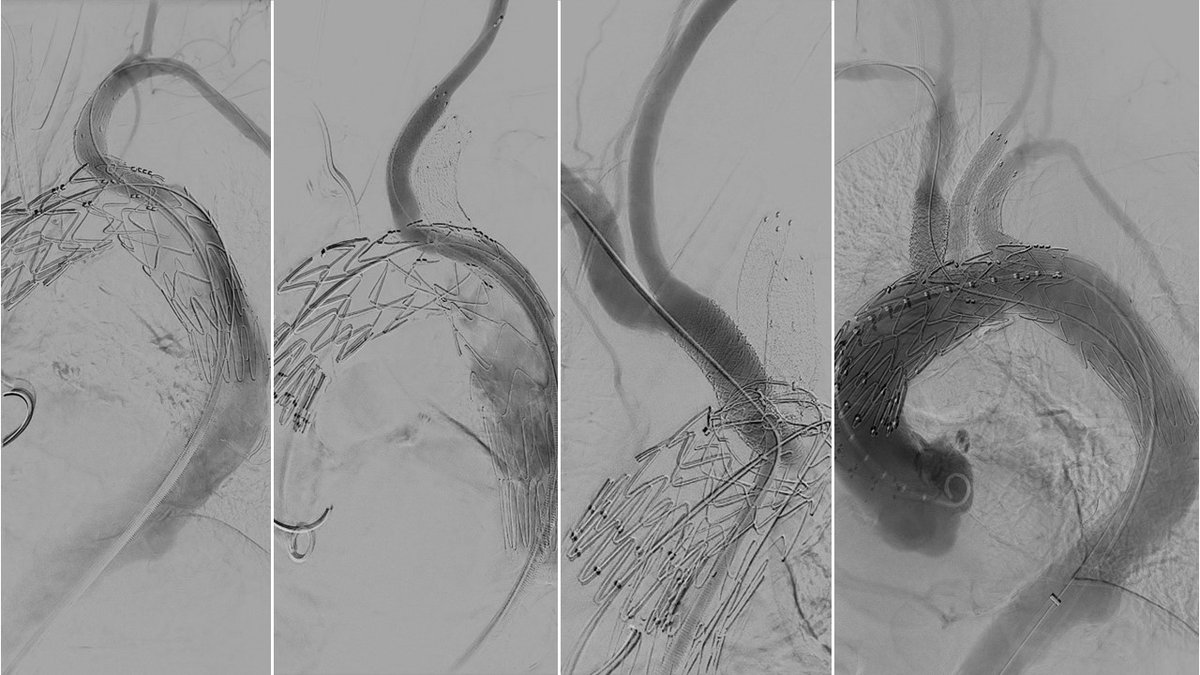

First implantation of a 3 retrograde branch aortic arch device using only groin access. Grateful to Cook Medical for the opportunity to collaborate and innovate.

First implantation of a 3 retrograde branch aortic arch device using only groin access. Grateful to <a href="/CookMedical/">Cook Medical</a> for the opportunity to collaborate and innovate.